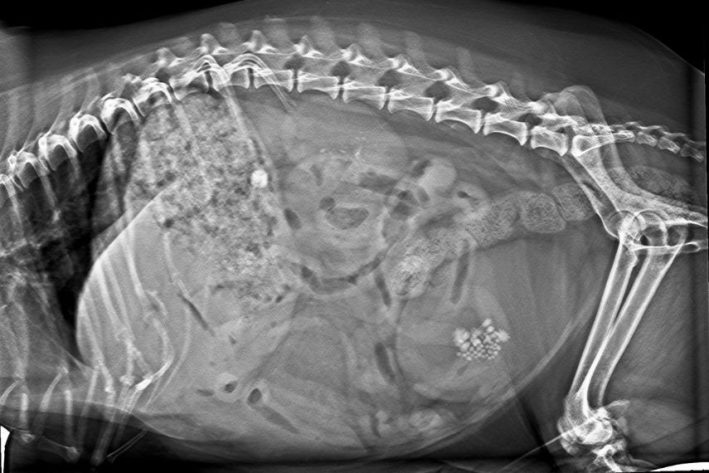

Bildgebende Diagnostik: Mittels Röntgen können röntgendichte Harnsteine sichtbar gemacht werden. Eine Ultraschalluntersuchung ermöglicht eine detaillierte Aussage zur Schleimhautbeschaffenheit und dem Harnblaseninhalt. Weiters kann ultraschallgestützt eine sterile Punktion des Harns vorgenommen werden.

Zystitits Roentgen

Zystitits Röntgen